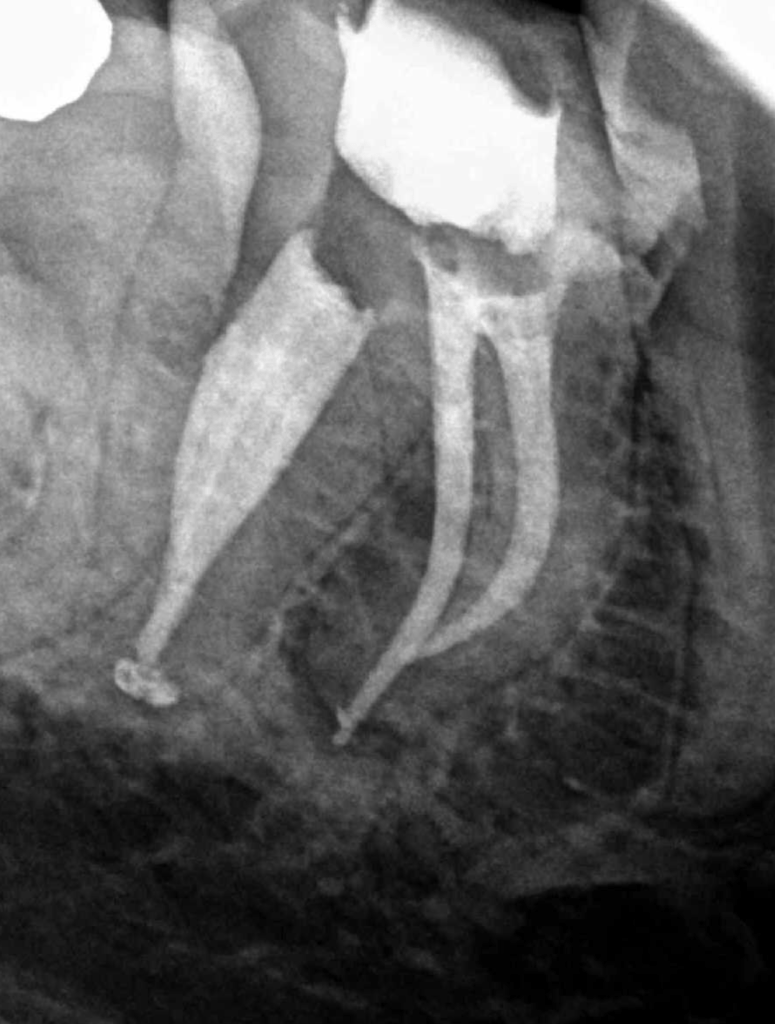

Reco preendo + 4 conductos molar superior